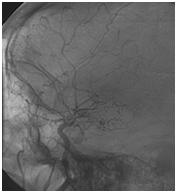

Mujer de 46 años que ingreso por cefalea súbita, hemiparesia izquierda y disartria, con tomografía axial computarizada cerebral simple que mostró hemorragia frontoparietal derecha drenada a ventrículos y arteriografía con patrón Moyamoya. Reingreso 3 meses después con deterioro del estado de consciencia y tomografía axial computarizada cerebral simple que mostró hemorragia intraparenquimatosa temporoparietal izquierda con extensión intraventricular y desviación de la línea media, se manejo en Unidad de Cuidados Intensivos con traqueostomía y gastrostomía, presentó neumonía y sepsis nosocomial, finalmente falleció en la Unidad de Cuidados Intensivos.